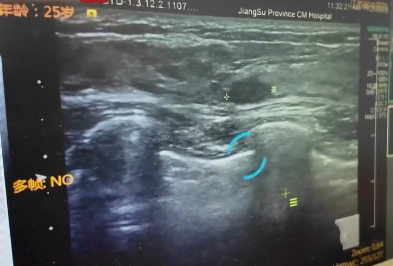

▲女子患上「乳腺癌」。(圖/翻攝自微博)